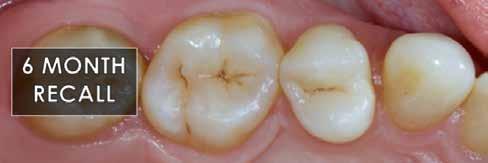

9. ábra: Hat hónapos kontroll.